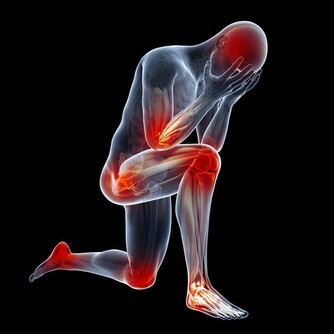

2.腹痛

腹痛也有可能是直腸癌的症狀。因為由於腸道功能紊亂,或者腸道梗阻而致。部位多集中在中下腹部,多為隱痛或脹痛,還有漸漸加重的趨勢。